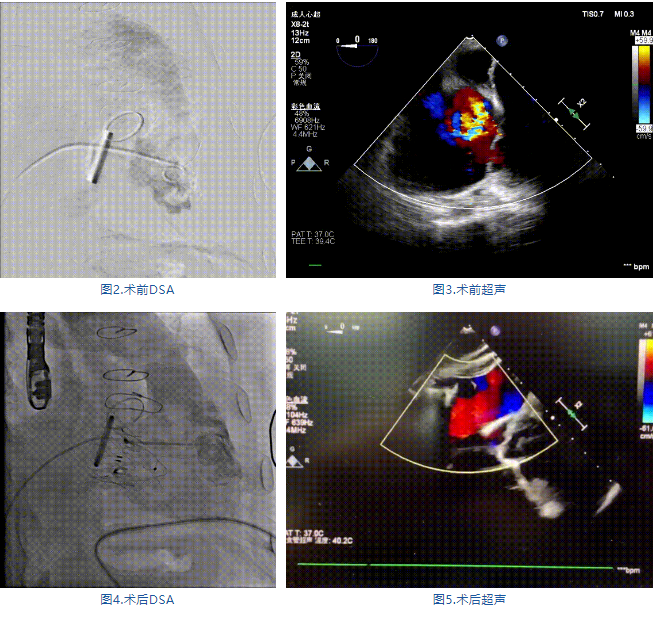

手術(shù)在全麻狀態(tài)下進(jìn)行,郭惠明教授團(tuán)隊采用經(jīng)右側(cè)頸靜脈入路的方式送入輸送器進(jìn)入體內(nèi),并在TEE和DSA的指引下進(jìn)行。在輸送器進(jìn)入右室后釋放室間隔錨定裝置,旋轉(zhuǎn)輸送器,使得錨定裝置對準(zhǔn)室間隔面;而后釋放前瓣夾持件,確定夾持件位于右室側(cè)釋放LuX-Valve Plus人工瓣膜盤片,再使用DSA和超聲確認(rèn)盤片是否位于右房側(cè),同時調(diào)整瓣膜的同軸性。緊接著在DSA和超聲的監(jiān)視下調(diào)整室間隔錨定件貼合室間隔,釋放室間隔錨定裝置。再次確認(rèn)瓣膜的穩(wěn)定性和同軸性后,將輸送器撤出體內(nèi),最終完成LuX-Valve Plus人工瓣膜植入(圖2-5),手術(shù)獲得圓滿成功?;颊咴谑中g(shù)室即刻拔除氣管插管,術(shù)后超聲提示LuX-Valve Plus人工三尖瓣瓣膜同軸性良好,瓣架固定牢靠,無反流和瓣周漏。